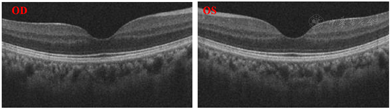

先证者欧堡示双眼黄斑区劈裂呈现轮辐状外观,周边部视网膜皱褶。OCT示双眼黄斑区视网膜呈现囊样扩张改变,其囊腔中被垂直的桥状组织所分割,无炎症渗出性改变,右眼较左眼明显(图2)。ERG示暗适应状态下,视杆细胞振幅重度降低,潜时延长;明适应状态下,视锥细胞振幅重度降低,潜时延长。

先证者弟弟(Ⅲ-2)眼底照相示双眼黄斑区劈裂隐约呈现轮辐状外观。OCT示双眼黄斑区视网膜呈现囊样扩张改变,其囊腔中被垂直的桥状组织所分割,无炎症渗出性改变(图3)。